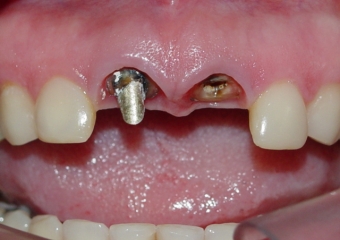

Raio X do implante